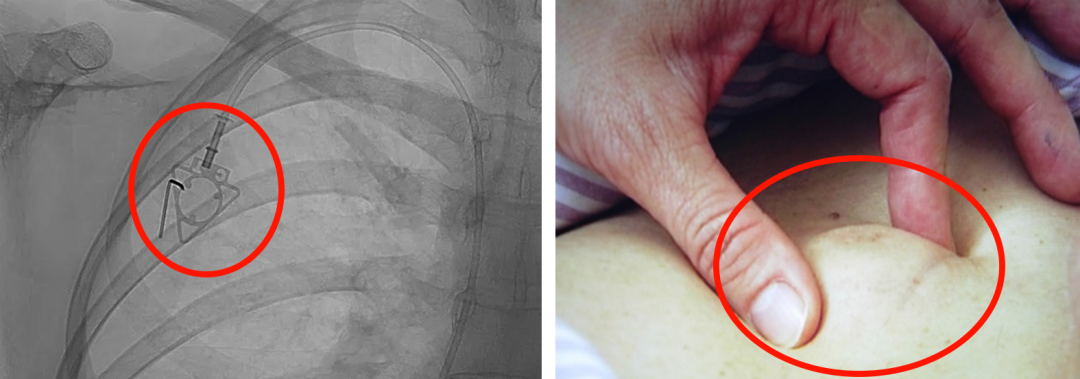

輸液港,臨床上也稱(chēng)為PORT,是為了減輕藥物對(duì)患者血管刺激而置入體內(nèi)的專(zhuān)業(yè)輸液裝置。它分為三部分:無(wú)損傷針、置入靜脈的導(dǎo)管、埋藏在皮下與輸液針連接的注射座(港體)。注射座連接插入大靜脈的導(dǎo)管形成長(zhǎng)期血管通路,發(fā)揮類(lèi)似港口的作用,故稱(chēng)作“輸液港”。